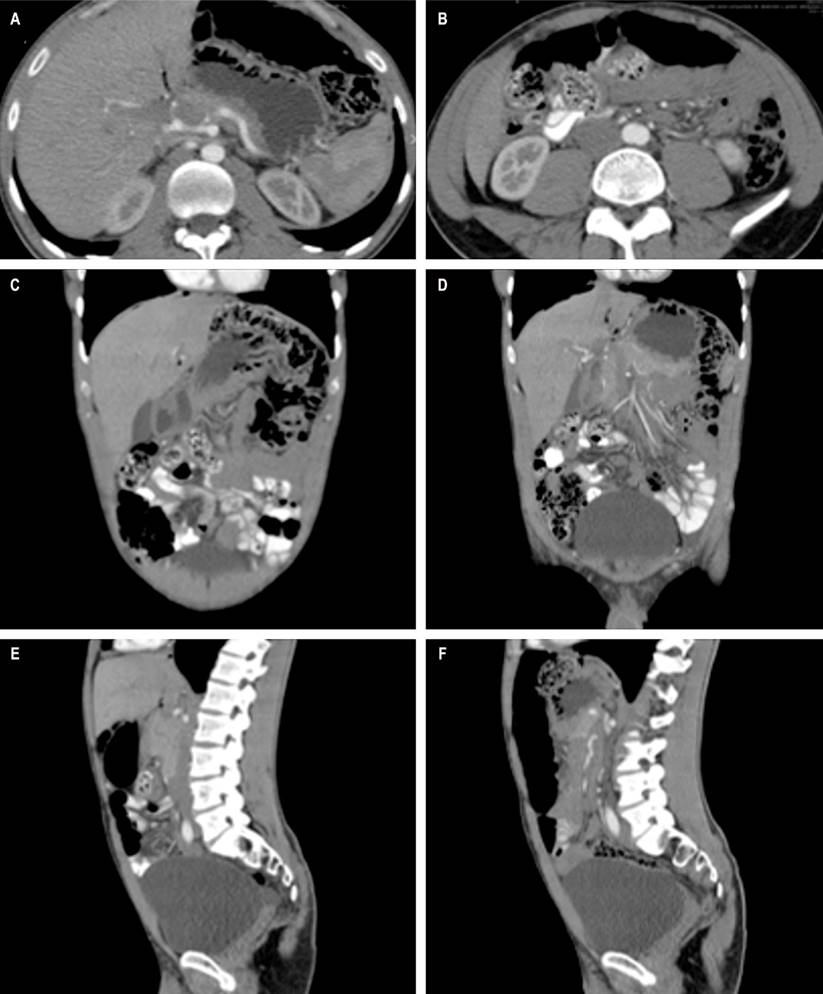

La TAC de abdomen con contraste mostró múltiples burbujas de aire de paredes delgadas, sin extravasación de medio de contraste, predominantemente de distribución perihepática y, en menor grado, subfrénica izquierda (Figuras 2A y B), con múltiples burbujas de aire extraluminales, localizadas especialmente en las paredes de colon descendente y sigmoide (Figuras 2C y D), algunas de ellas en racimos, adheridas y adyacentes a una “cámara de neumoperitoneo encapsulada” de aproximadamente 160 mm de diámetro mayor en vecindad con el ángulo esplénico (Figuras 2E y F), compatibles con los hallazgos endoscópicos de PCI.

Figura 2 TAC de abdomen. A y B. Corte sagital. Neumatosis quística colónica en racimo, con múltiples burbujas de aire de paredes delgadas, sin extravasación del medio de contraste. C y D. Corte coronal. Múltiples burbujas de aire extraluminales, localizadas en las paredes del colon descendente y sigmoide. E y F. Corte axial. Neumoperitoneo en el abdomen anterior, de 16 cm de diámetro en vecindad con el hígado y en continuidad con las burbujas del ángulo esplénico del colon. Fuente: archivo de los autores.